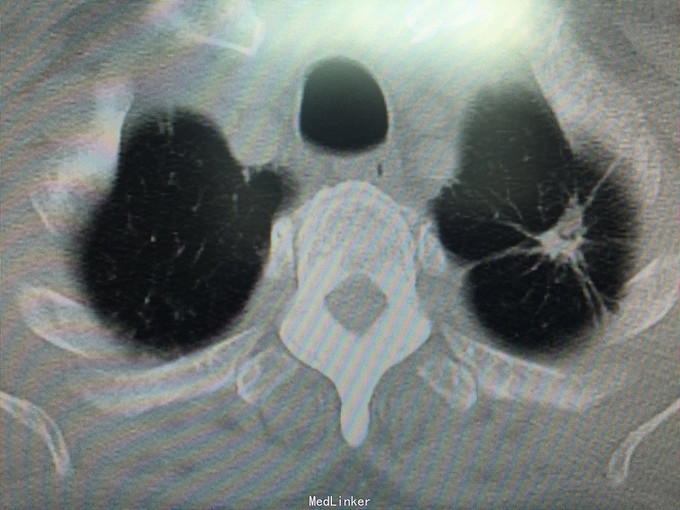

男性,70岁, 主诉:发现左肺上叶占位12个月 现病史:2014.10月患者出现胸背部疼痛不适,对症理疗未见好转。2014.11月出现咳嗽,咳痰带血丝,行胸部CT检查示:左肺上叶占位病变,恶性可能性大。2014.11.13患者行PET/CT检查提示:左肺上叶软组织密度肿块影伴周围片状密度增高影,代谢增高,考虑恶性病变伴周围炎性改变。纵隔内及左肺门多发淋巴结影,代谢增高,考虑为恶性病变转移。左肾上腺结节,代谢增高,考虑为恶性病变转移。第2胸椎棘突骨质破坏,代谢增高,考虑为恶性病变转移。肿瘤标志物:CA125 625 U/ml。因肿块位置较高,未行纤维支气管镜取病理,患者因年龄大,拒绝行肺肿物穿刺活检,故病理不明确。但根据肿瘤影像学形态及理化检测,怀疑为腺癌,建议患者行TKI靶向治疗,同时给予双磷酸盐治疗骨转移。患者口服TKI一个月后复查胸部CT肿块明显缩小,胸背部疼痛消失。患者现口服TKI约11个月,无明显咳嗽咳痰,无背部疼痛。近1周,患者诉偶尔咯鲜红色粘痰,伴有咽部及胸前区闷痛疼痛无明显咳嗽症状,为求复查而来诊。复查胸部CT较之前对比未见明显变化。复查肿瘤标志物:CEA、CA-125、NSE均未见异常。

查体:BP 165/75mmHg,双肺呼吸引清,未闻及干湿罗音,心音钝,心律齐,心率72次/分,各听诊区未闻及杂音。腹平,未见胃肠型及蠕动波,腹软,全腹无压痛,无反跳痛及肌紧张,肝脾肋下未触及,墨菲氏征(-),移动性肝肾区无叩痛,移动性浊音(-),肠鸣音4次/分。 辅助检查:肝胆脾彩超:未见明显异常。 胸部CT:较2015.8月对比未见异常,左肺上叶陈旧性改变。 肿瘤系列:CEA、CA-125、NSE均未见异常。